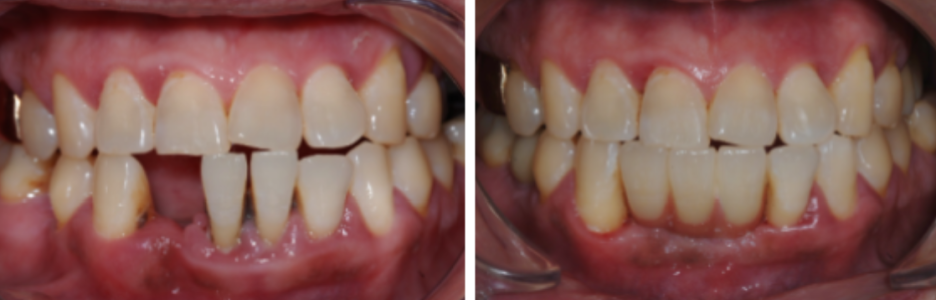

< Some implant surgery cases >

Treatment period: 23.12.25 - 24.6.28

Problem tooth location: maxillary anterior region

Treatment period: 21.6.23 - 22.4.8

Problem tooth location: mandibular anterior region